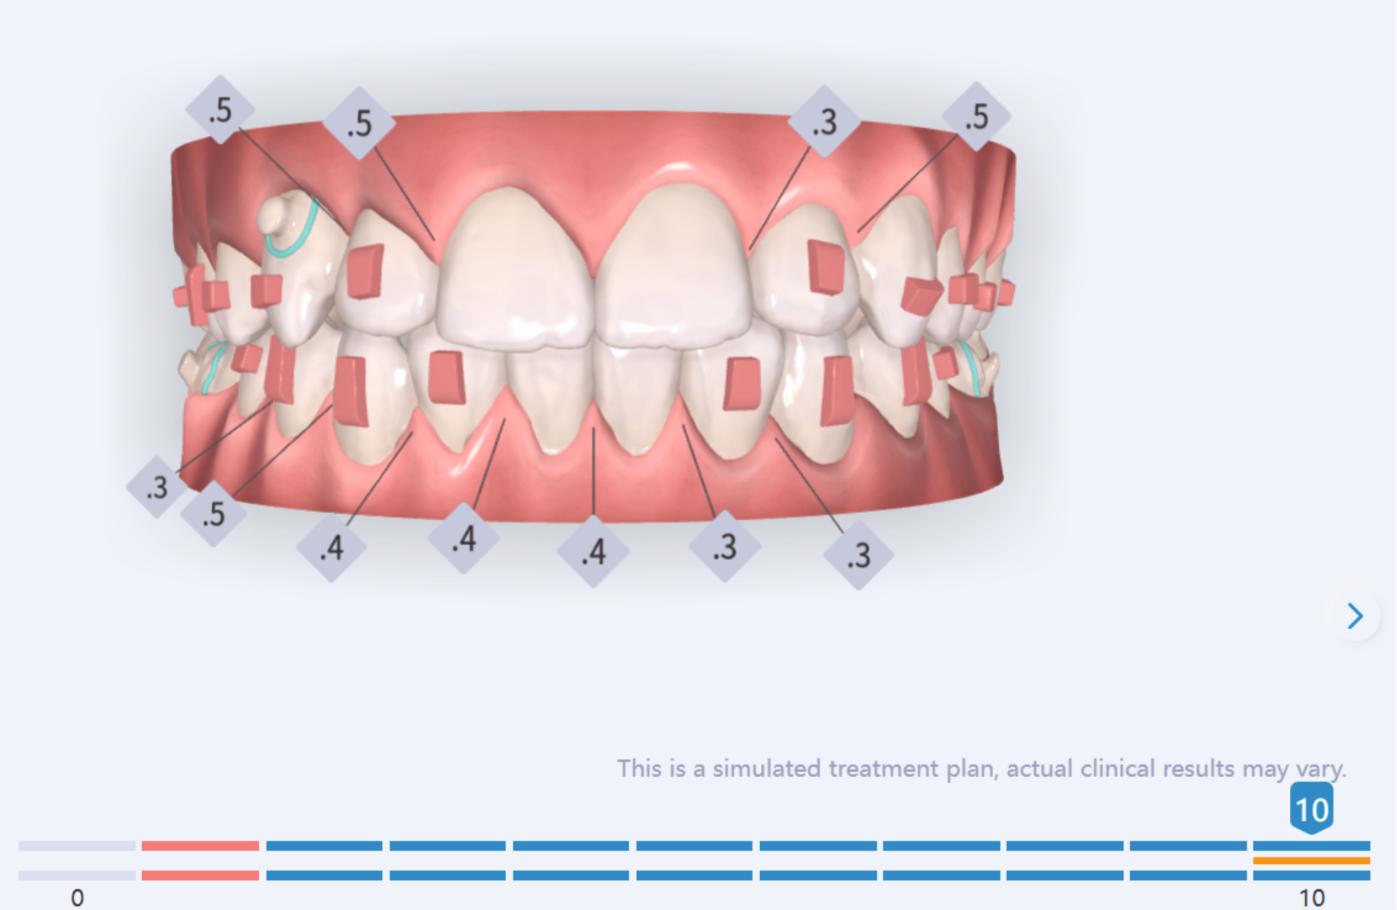

We approached the case by combining upper distalization using the A8 protocol with an asymmetric virtual jump. In this way, we solved the crowding without proinclining the incisors and improved the anteroposterior relationship through the use of elastics. In the lower arch, we carry out a development of the posterior sectors prior to the resolution of the crowding, in order to avoid roundtripping and excessive IPR of the incisors. To achieve an effective extrusion and distalization of 13, we combine the use of direct bonding button on vestibular of 13, with angelButton elastics mesial and distal to the canine. These mechanics help to ensure that the extrusion is real and that the aligner always remains adapted.

Treatment details

In the upper arch, the main goal will be to correct the Class II malocclusion by distalizing the upper posterior teeth in order to resolve crowding without proinclining the incisors. This movement will be accompanied by an asymmetric “bite jump” of 1 mm, which will help improve the skeletal Class II discrepancy, promoting mandibular projection, especially considering that the patient is still in the growth phase. Additionally, bilateral and symmetric expansion will be planned until a torque of 0° is achieved, allowing for proper transverse alignment and greater stability of the final result. Lingual button cutouts will be placed on teeth 14 and 24 to facilitate the required movements. To optimize control and retention, vertical mesial beveled attachments, as large as possible, will be placed on the premolars and molars, as well as on teeth 12 and 22, reinforcing the mechanics in the anterior sector. The inclination of the central incisors 11 and 21 will be corrected according to the visual reference provided in the clinical image. Furthermore, it will be necessary to center the upper midline by shifting it 0.5 mm to the left to achieve greater aesthetic symmetry. As for the lower arch, treatment will begin with a phase of expansion and derotation of the posterior teeth, which will set the stage for subsequent movements in the anterior sector. Once this goal is achieved, alignment of the teeth from canine to canine will proceed, aiming to minimize anterior interproximal reduction (IPR) and avoid unnecessary round- tripping movements of the incisors. Vestibular button cutouts will be made on teeth 36 and 46, while teeth 37 and 47 will have horizontal attachments that will serve as anchorage to ensure stability during treatment.